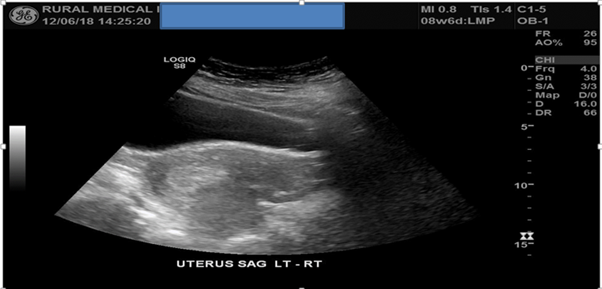

The LNMP dates and personal details were inputted into the ultrasound machine which corresponded with that of the GP’s referral (8 weeks and 6 days gestation). The exam commenced by utilising the C1-5 MHz TA probe. The patient was prepared with a distended bladder for the efficient propagation of high frequency soundwaves through the bladder which acts as an acoustic window to increase the clarity of the uterus, cervix and ovaries situated posteriorly. A full scan throughout the uterus from the left to right margins in a “sweeping” motion in longitudinal plane commenced. The same scan was commenced now in the transverse plane scanning through the superior fundus inferiorly towards the internal os. Multiple images were acquired during the scan of the uterus in both planes which concluded that no GS or IUP was currently present, it is also noted that the uterus is anatomically retroverted and that no pathology such as free fluid was located in the POD.

Figure 1: TAS of the uterus in both longitudinal and transverse planes failed to detect a GS or IUP.